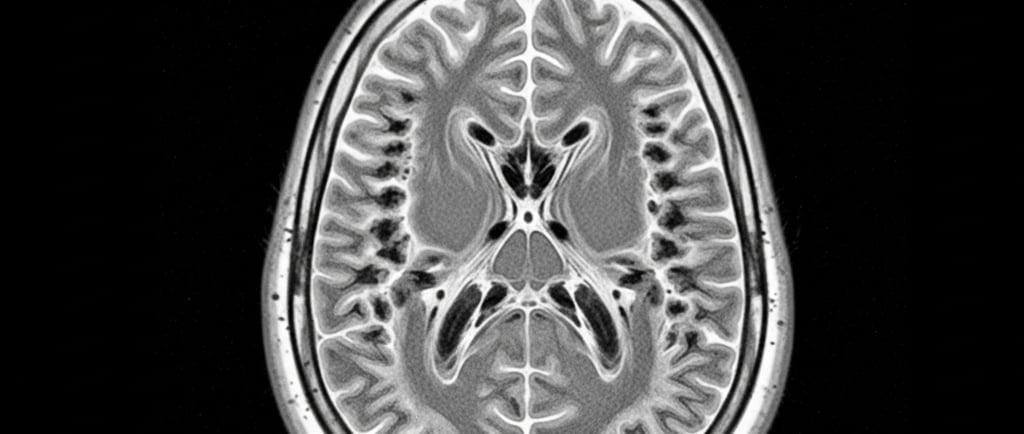

Ressonância Magnética (RM) do cérebro com achados típicos na substância branca; 2) Teste genético para confirmar duas alterações no mesmo gene EIF2B. Se a RM “bate” com VWM e só aparece uma alteração, o time médico precisa procurar a segunda; se nenhuma é encontrada, é preciso buscar outra causa. Por vezes, centros de referência em leucodistrofias ajudam a interpretar exames de imagem e genética.